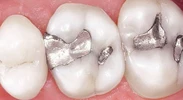

Diş Çürükleri